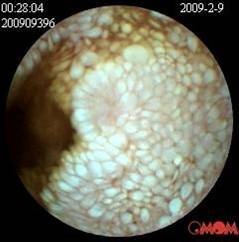

小肠淋巴管扩张症

医学课堂︱一例结直肠血管扩张症患者的诊断与分析